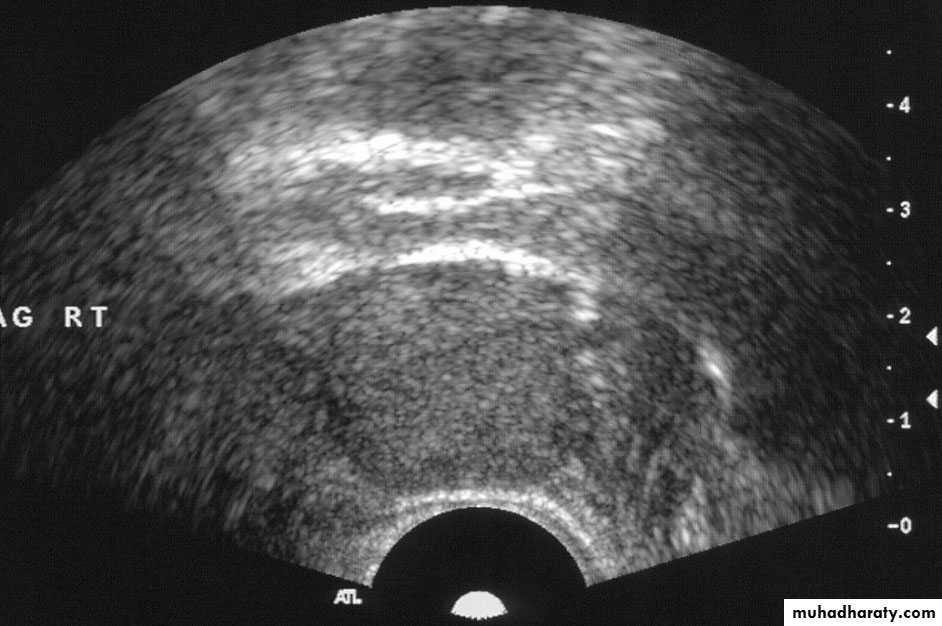

• Transvaginal US (TVUS): accurate assessment of gynecological problems and of early pregnancy up to about 12 weeks’ gestation

• Transrectal US (TRUS): guidance of prostate biopsy; staging of rectal cancer

• Transcranial US: neonatal brain and TCD.